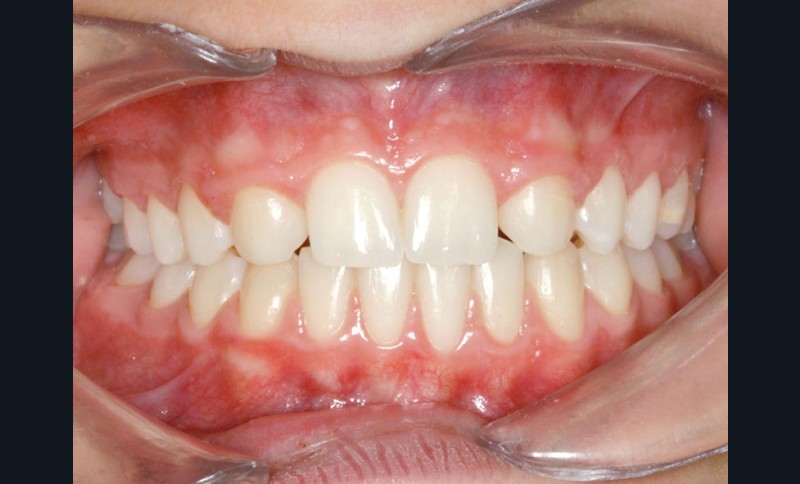

Le traitement orthodontique sans extraction à l’arcade mandibulaire a permis d’établir une occlusion de classe II thérapeutique équilibrée et un sourire harmonieux (fig. 4 et 5).

Une discrète coronoplastie par soustraction a adouci les contours des pointes cuspidiennes canines.